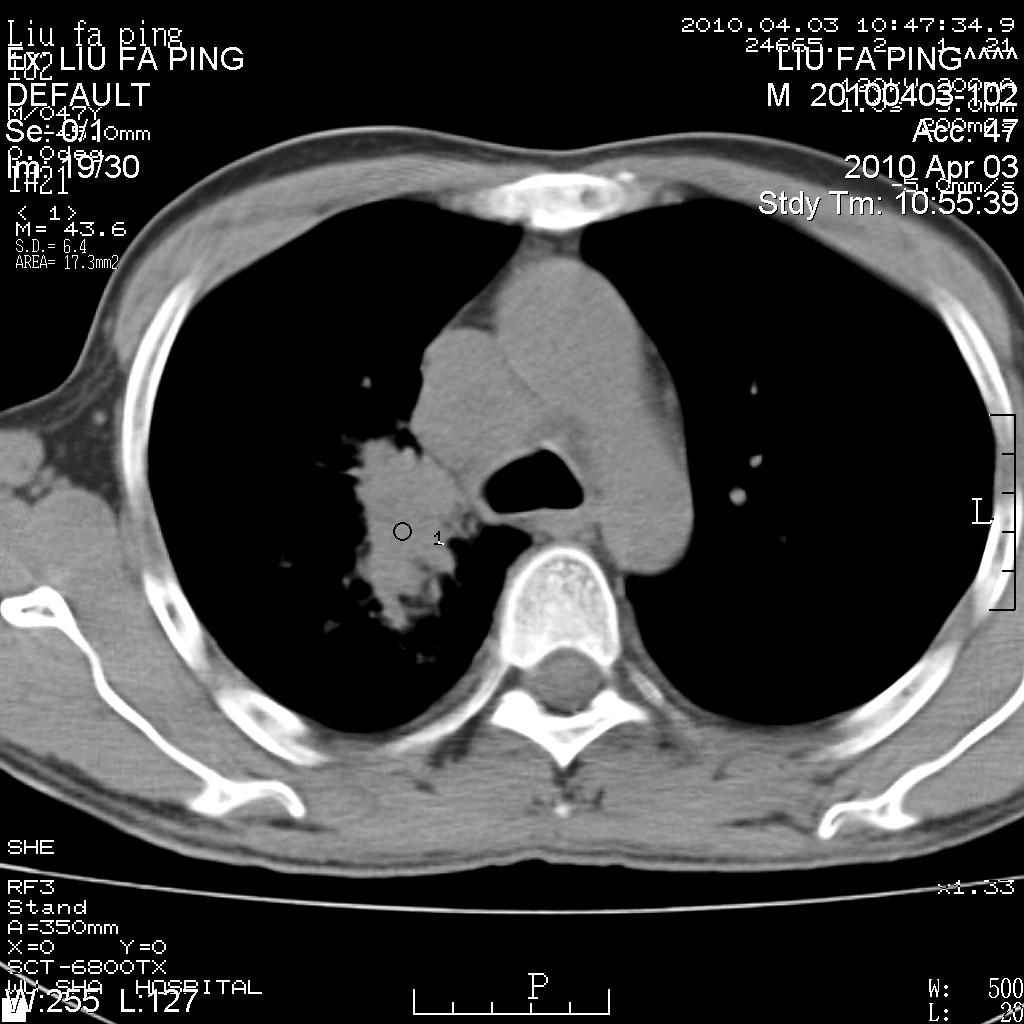

标题: CT25875:咳嗽数天。 [打印本页]

标题: CT25875:咳嗽数天。

平时身体健康,无不适

男性47岁,考虑中心性肺癌合并阻塞性肺炎,纵膈淋巴结肿大。肺内及纵膈淋巴结钙化。

建议支气管镜检

支持右侧中央型肺癌伴右肺上叶阻塞性炎症,建议纤支镜检查!

支持右侧中央型肺癌伴右肺上叶阻塞性炎症、纵膈淋巴结转移,建议纤支镜检查!

男性47岁,考虑中心性肺癌合并阻塞性肺炎,纵隔淋巴结肿大。肺内及纵隔淋巴结钙化。

考虑右肺中央型肺癌并阻塞性肺炎,右肺门及纵隔淋巴结转移;建议必要时行纤支镜检查进一步明确诊断。